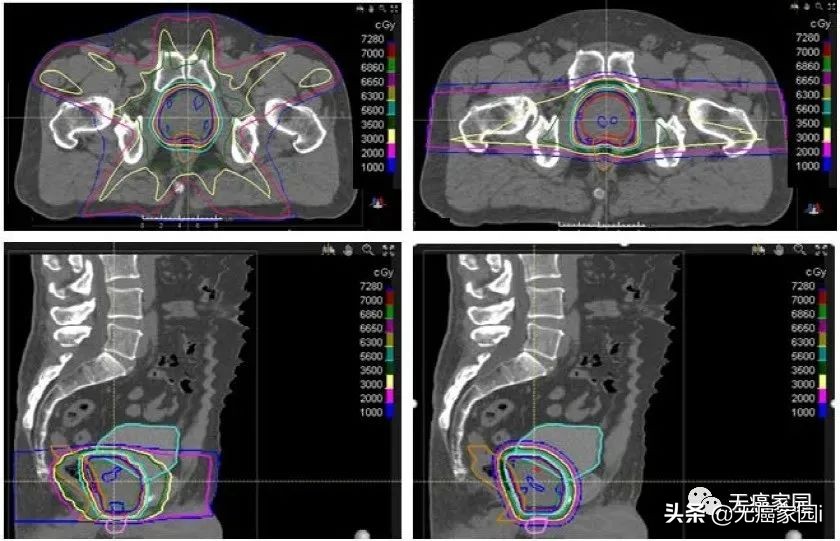

调强适形放疗(IMRT)与质子治疗前列腺癌的剂量比较。质子治疗计划减少了膀胱、直肠和阴茎球的辐射剂量,但增加了股骨头的剂量。两个计划与处方等剂量线的适形性相似。

图为质子治疗与IMRT治疗食管癌的剂量学比较,左为质子治疗,右为调强放疗

(注:Dmax,最大点剂量;Vx,体积乘以Gy的x剂量;MLD,平均肺部剂量;MHD,平均心脏剂量;MLivD,平均肝脏剂量;MKD,平均肾脏剂量)